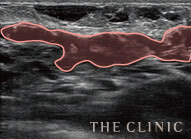

ヒアルロン酸豊胸後に生じたしこり(エコー画像)と実際に除去したヒアルロン酸

-

溶解液注入   的確にしこりへ穿刺・注入

吸引・除去後   しこりの消失を確認

除去したヒアルロン酸   目視することで確実に除去